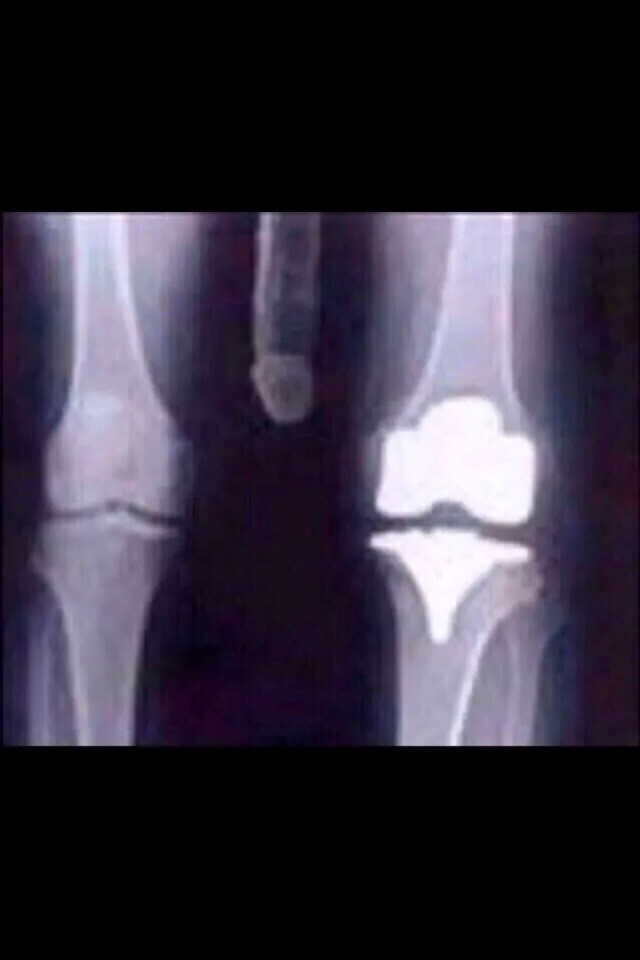

You may not have heard but I have recently had to have my left knee replaced.

It was all a bit sudden but I was getting quite a bit of pain.

The Specialist said it was arthritis caused by old Rugby injuries and prospecting.

I am still on crutches, it is a lot better and I no longer have any stiffness.

The Hospital has sent me a copy of my XRay of the replacement..below....and all looks better than most.....